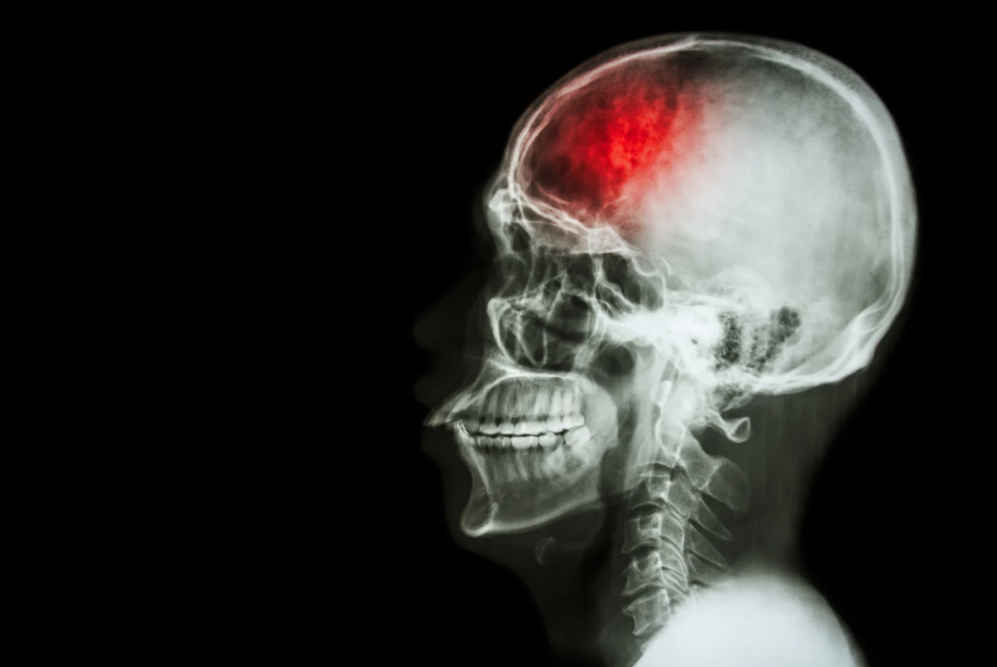

WHAT IS HAEMORRHAGIC STROKE?

A haemorrhagic stroke claimed Iskandar’s life. While ischemic strokes - which happen when blood flow to the brain is blocked - are more common, haemorrhagic strokes occur when a blood vessel in the brain breaks and bleeds.

"A haemorrhagic stroke involves spontaneous bleeding in the brain caused by a ruptured blood vessel, which then disrupts brain function.

"This condition occurs when the blood vessel walls become thinner and in most cases, it is triggered by high blood pressure,” Dr Nor Faizal explained.

Dr Nor Faizal said a haemorrhagic stroke can only be confirmed through a CT scan because its symptoms are similar to other types of strokes.

"In terms of treatment, a haemorrhagic stroke requires immediate surgery to relieve pressure on the brain caused by sudden bleeding inside the blood vessels.

"Imagine the brain as a container with a limited capacity. When there is a sudden increase in blood volume, it puts pressure on the brain tissue, which can then stop functioning properly.”